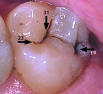

Diagnodent laser detection can catch problems before they begin!

Sharp explorer may not detect

cavity. Diagnodent laser finds hidden cavity.